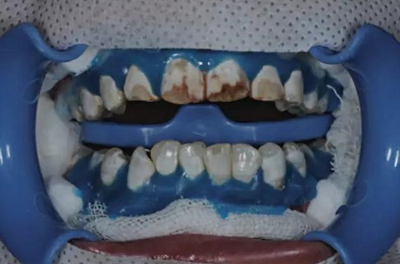

1、利用高速渦輪機(jī)配105 um金剛砂車針 (ML524, Diatech, Altstatten, Switzerland) 磨除200-400 um的牙釉質(zhì)。

2、利用中-細(xì)拋光盤 (Sof-Lex, 3M ESPE, St Paul, MN, USA) 打磨釉質(zhì)表面并消除尖銳角。

3、在牙頸部涂布光固化的牙齦保護(hù)劑 (Beyond Technology Inc, Santa Clara, CA, USA),在釉質(zhì)表面涂布含硅脲微粒和6.6%鹽酸的研磨膏 (Opalustre, Ultradent Products, South Jordan, UT, USA),利用橡皮杯 (Oralcups, Ultradent Products) 微打磨120 s。

4、微打磨后,利用診室內(nèi)漂白劑 (Opalescence Boost, 38%H2O2 Ultradent Products) 減輕氟斑牙表面的棕色著色。

隨后,在牙面上涂布抗敏感保護(hù)劑(Fluorinated protector, Beyond Technology Inc),停留5 min后吸除,水徹底沖洗牙釉質(zhì)表面并移除牙齦保護(hù)劑。

在診室內(nèi)漂白的同時(shí)聯(lián)合運(yùn)用家庭漂白。在使用8支10%過氧化脲凝膠 (Ultradent Products) 后,患者很滿意漂白效果。

5、由于氟斑牙存在釉質(zhì)礦化不全等問題,家庭漂白兩周后,使用標(biāo)準(zhǔn)的樹脂滲透技術(shù) (Icon, DMG Products, Hamburg. Germany) 來預(yù)防釉質(zhì)齲。最后,徹底改變患者的前牙美學(xué),并在一年后仍保持穩(wěn)定。